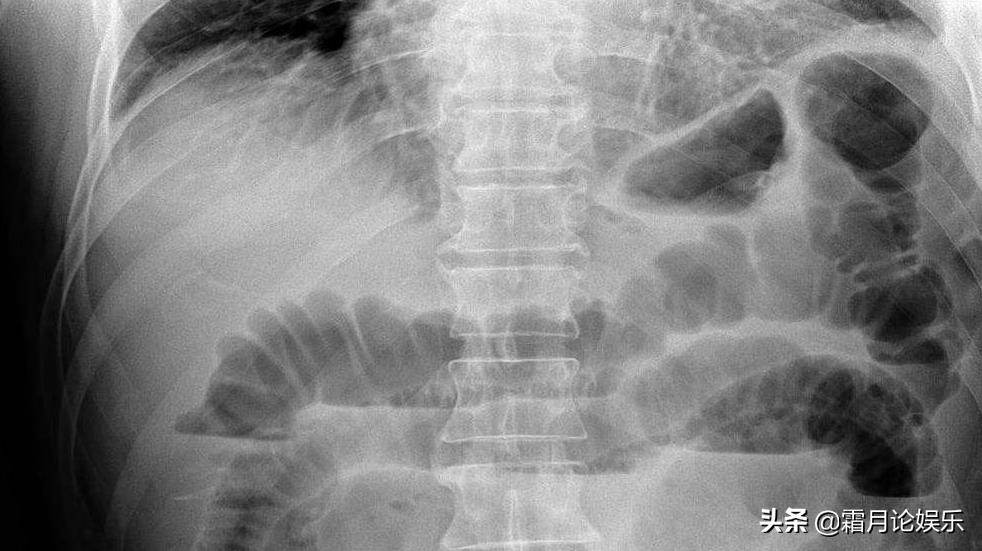

原来王越的身体里的恶性肿瘤已经扩散到了整个腹腔,并产生了极为严重的肠梗阻,这也就意味着她很快就无法进食了。

2016年,王越体内癌症再度恶化,医生说,她腹部的恶性肿瘤没有被化疗抑制住,癌细胞还在生长,而淋巴管还有血管也不正常,这恰恰也是所有癌症晚期的患者最担心情况,情形更加不乐观了。

连续多天,无法排气也无法排便,她的小腹开始肿胀得像个球一样。看着圆滚滚的肚皮,王越的情绪几度崩溃,这给她的感觉就像是肚子正在由内而外地烂掉。